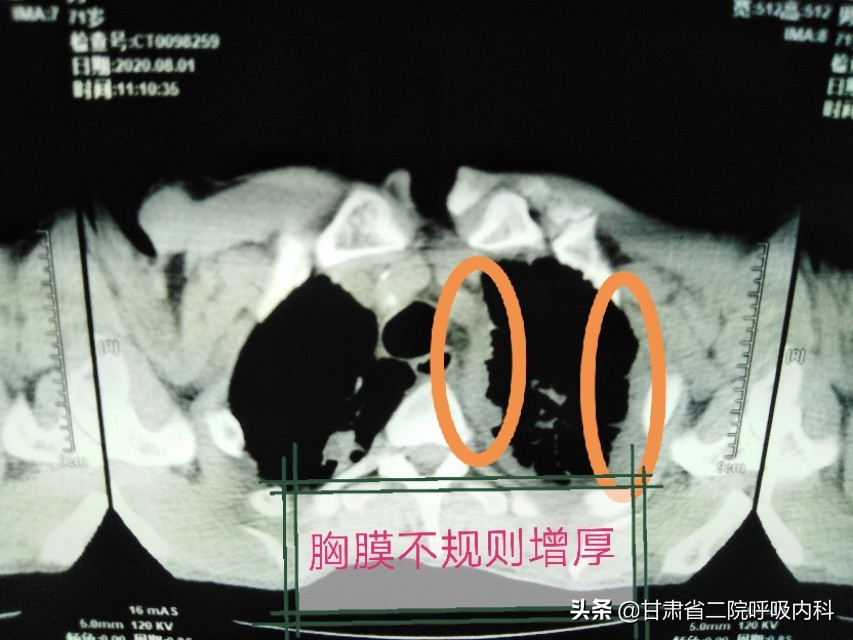

影像学可表现为结节性或弥漫性胸膜增厚、胸膜表面多结节性凸起、双侧胸腔积液、同侧肺体积减少等。

②弥漫性胸膜间皮瘤胸膜广泛结节状或不规则状增厚。胸腔积液。累及纵隔胸膜时,出现纵隔固定。纵隔内可见肿大淋巴结。